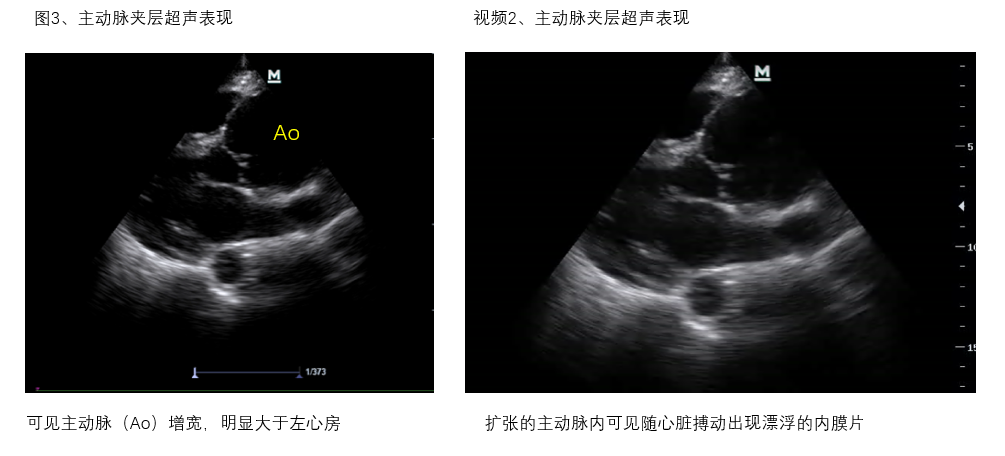

A、心包腔 观察有无心包积液,及其引起右心舒张受限、心包填塞导致循环衰竭的超声证据(图2、视频1)。此外,对于心包积液者,需谨慎观察有无主动脉增宽、漂浮的内膜片等夹层证据及心室壁不连续、异常血流通道等心脏破裂超声证据,区别主动脉夹层破裂、心脏破裂等原因引起的心包积血(图3、视频2)。

(图3、视频2)

视频2-主动脉夹层